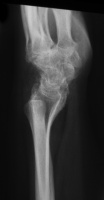

| She had progressive deterioration over two years with worsening pain and instability. |

| Eventually, she was treated with wrist fusion, distal ulnar resection and extensor carpi ulnaris tenodesis, and basal joint excision arthroplasty with split abductor pollicis longus anchovie interposition and ligament reconstruction - all through a single dorsal approach.: |